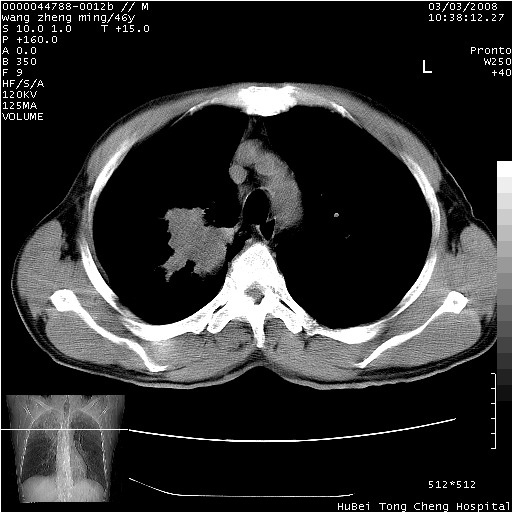

以下是引用卜一在2008-3-22 1:37:00的发言:[br]右肺实质性肿块,边缘不整,明显见毛刺征 分叶征及胸膜凹陷征,右上叶支气管明显变窄,远端散在的片状 斑片状实变影。另:左肺门较大肿块,支气管受累 变窄,远侧见阻塞性肺炎。纵隔内见肿大淋巴结。多考虑:右肺周围性肺癌伴左肺门 纵隔淋巴结转移!